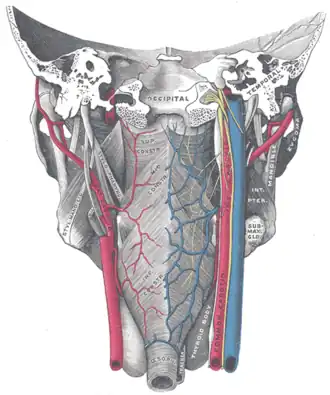

Muscles of the pharynx, viewed from behind, together with the associated vessels and nerves.

Muscles of the pharynx, viewed from behind, together with the associated vessels and nerves. -